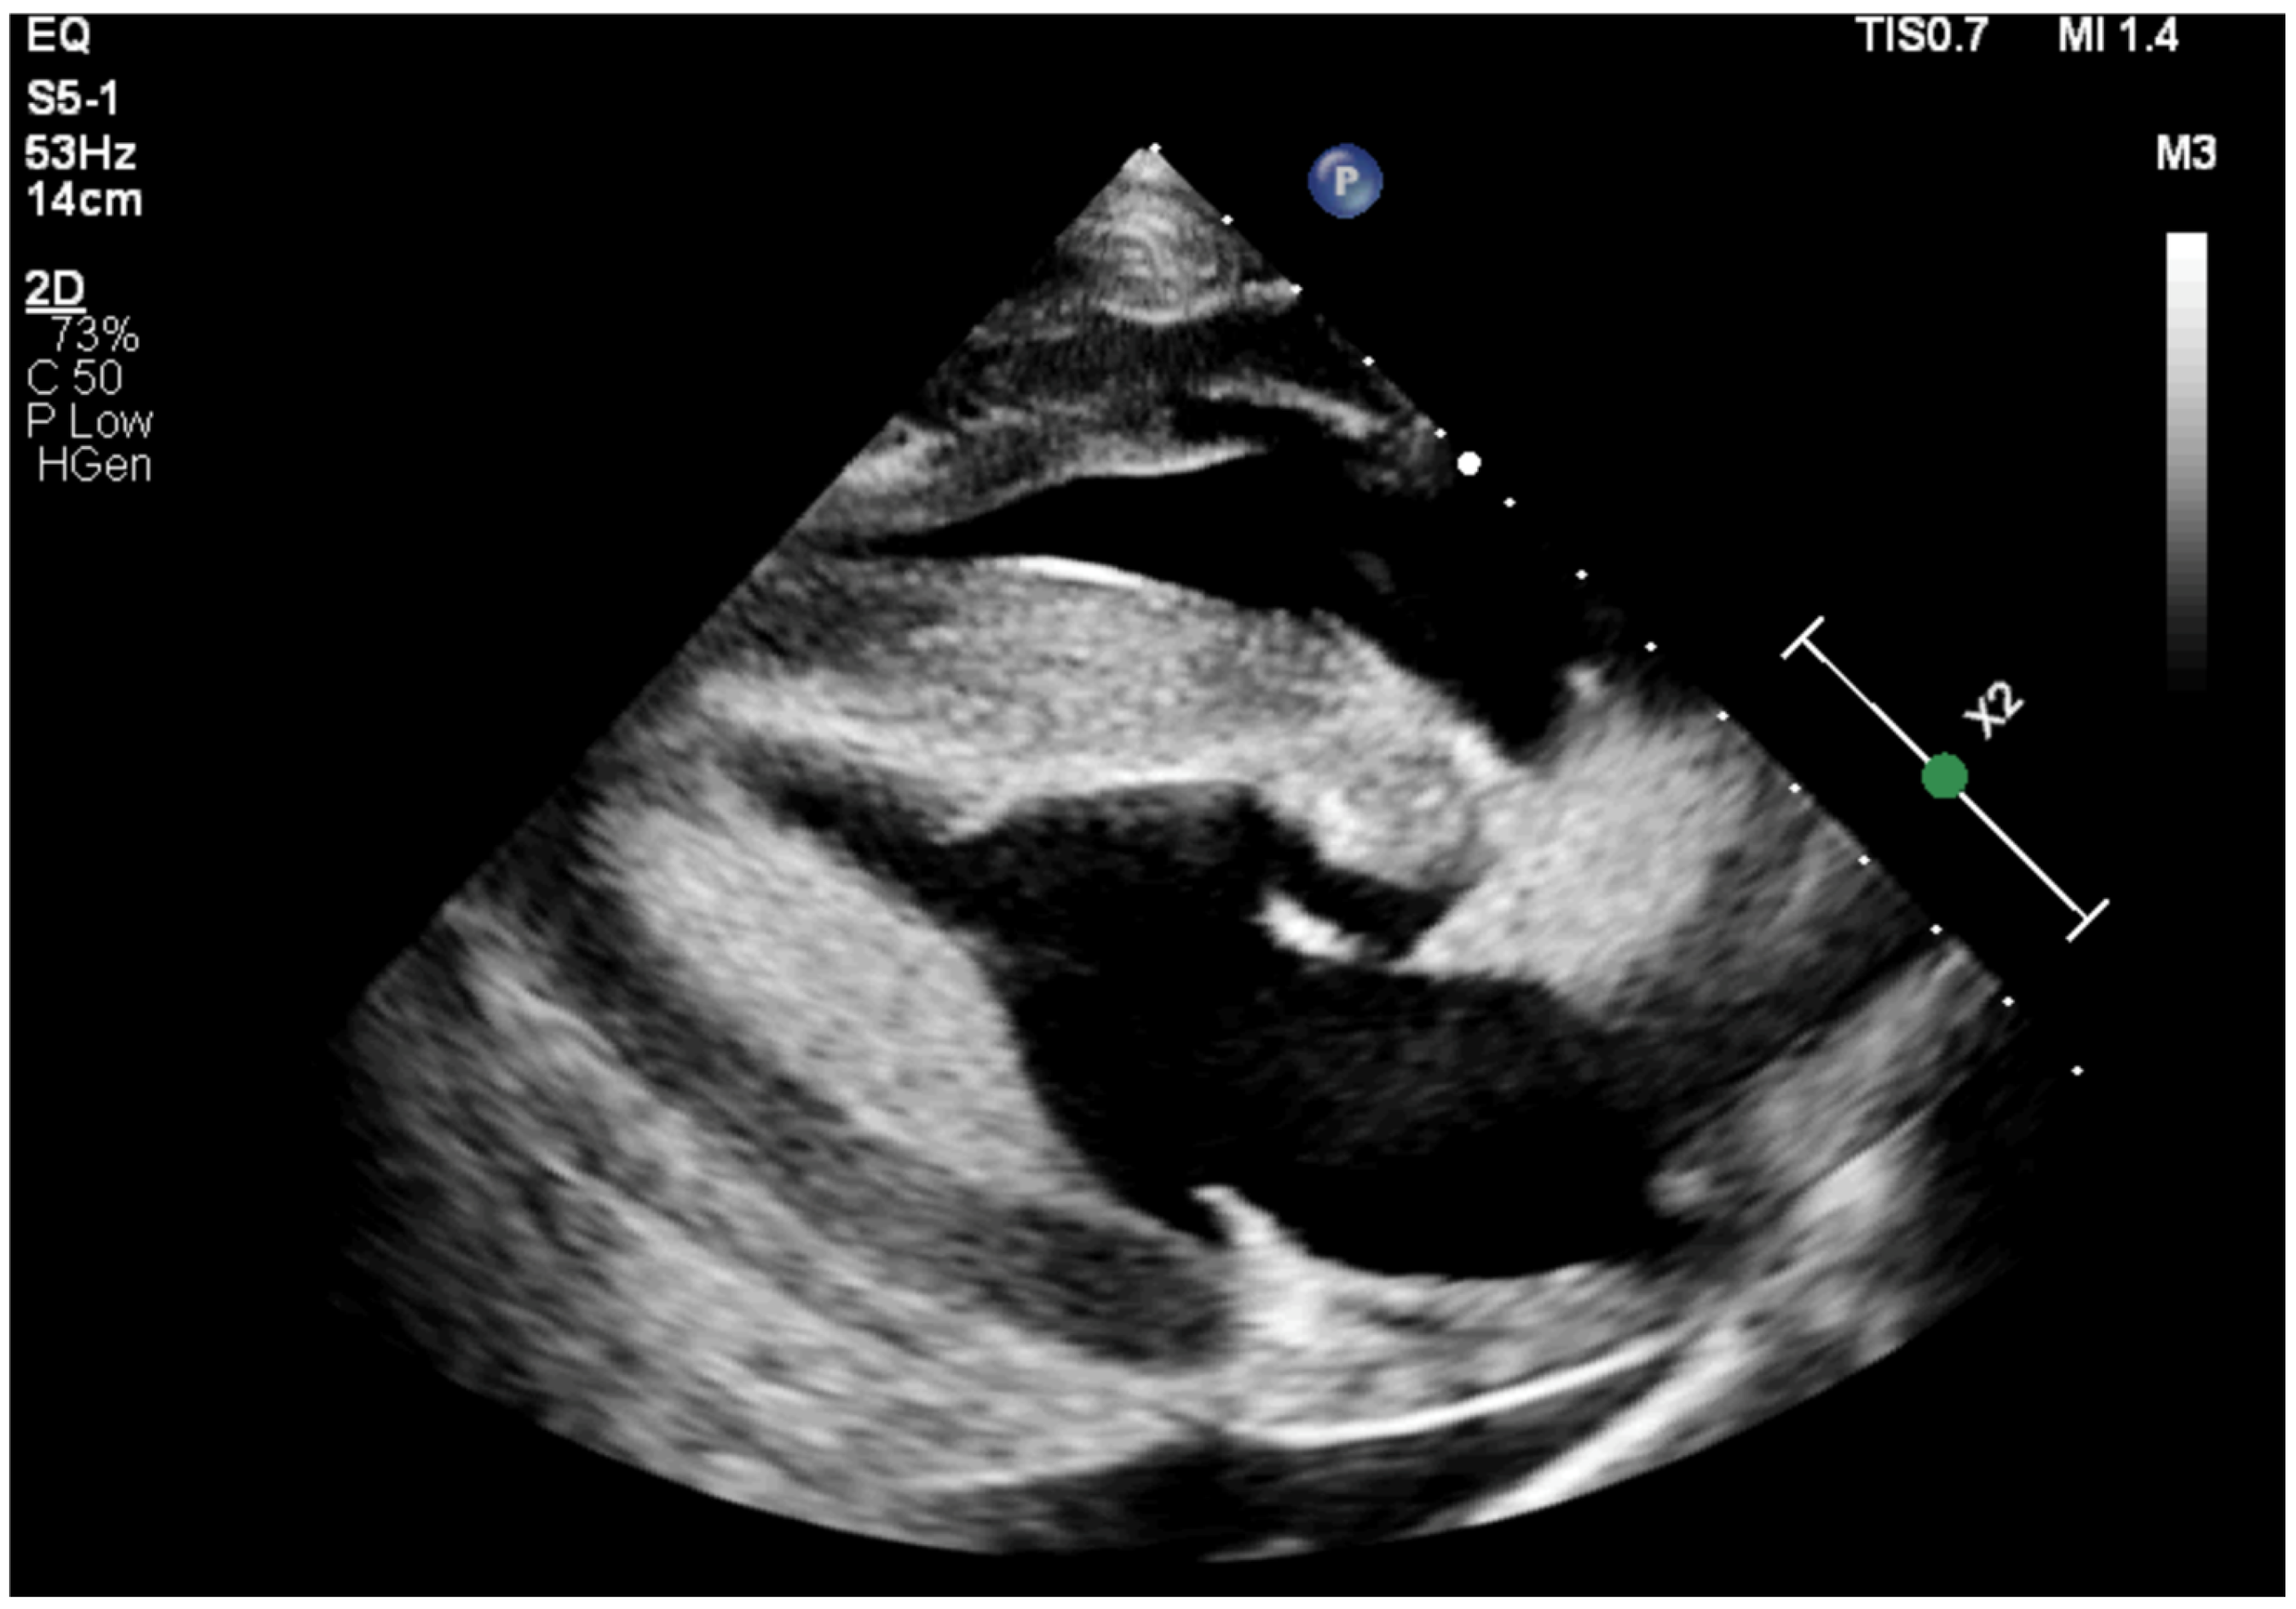

2.1. Case 1

2.2. Case 2

2.3. Case 3